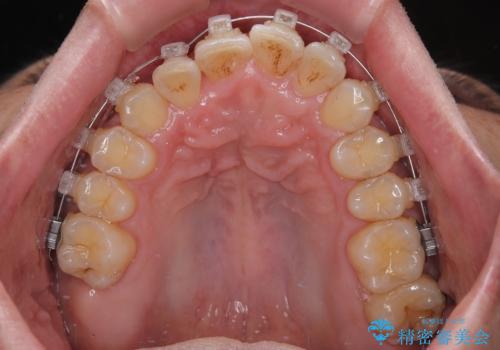

- クリアブラケット

- 1年1ヶ月

- 10-30回

ワイヤー矯正でもマウスピース矯正でも可能でしたが、短期間で、自身の手を煩わせることなく治療を行いたいとのことで、ワイヤー装置にて矯正治療を行うこととしました。

上顎前歯の舌側転位が顕著であったため、治療期間が長くなると思われましたが、僅か1年で無事に終えることができました。